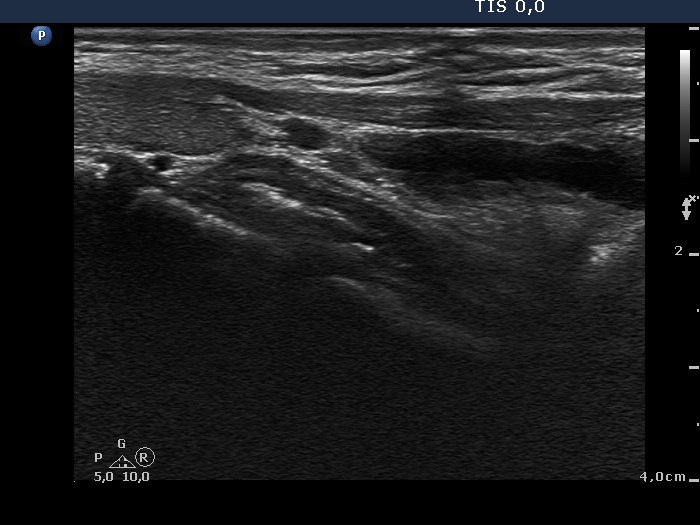

Parathyroid lesions - case cons100_028 (ultrasonographic picture 11)

Right lobe, longitudinal scan